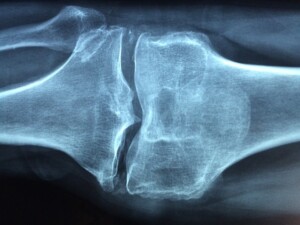

El diagnostico de ARTROSIS se realiza con una simple radiografia de las zonas dolorosas.

Este dolor e inflamación ARTROSICA afecta con mayor frecuencia a las pequeñas articulaciones de las manos y los pies. Sin embargo, otras como las rodillas, los codos o las del cuello también pueden verse afectadas, provocando la reducción del movimiento, lo que finalmente deriva en una merma de la calidad de vida.